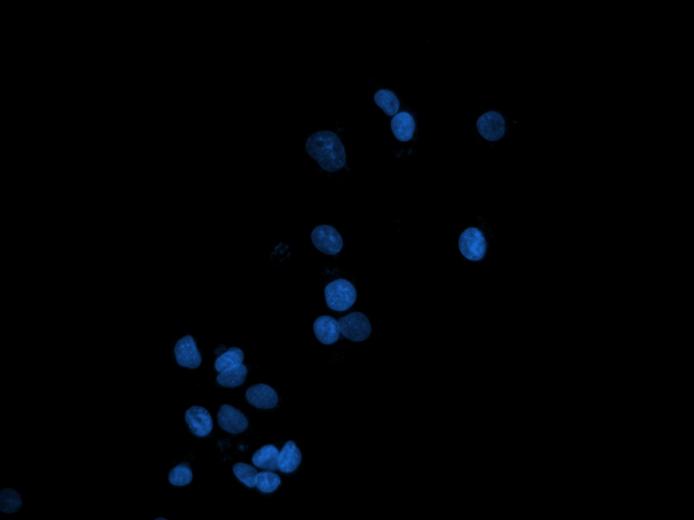

The aim of this project is to develop an objective and intelligent system that expresses the response of live cells to anticancer drug candidates in terms of cell death types and their quantities. This system intends to automatically analyze microscopic images and to automatically classify and quantify cell deaths under a microscope. The proposed project has five main steps. 1.) Growing live cell cultures in media that contain anticancer chemicals and acquiring their microscopic images, 2.) segmenting cells for the identification of their locations, 3.) extracting mathematical features from the segmented cells, 4.) classifying the cells as live or death (apoptotic, autophagic, or senescent) using these features and quantifying their indices, and 5.) developing a new anticancer drug screening test that is based on microscopic imaging and that uses the cell death information.